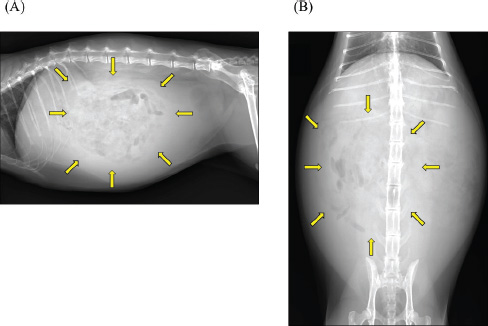

A 2-year-old castrated male domestic shorthair cat, weighing 5.3 kg, presented with a 2-month history of abdominal distension and a 4-day history of anorexia. There was no history of illness or abdominal surgery. Physical examination revealed severe abdominal distension with a fluid wave and mild hypothermia (37.1°C). Blood tests revealed mild elevations in blood glucose (178 mg/dl; reference interval 71–148 mg/dl) and serum amyloid A (5.27 µg/ml; reference interval <3.75 µg/ml) levels, while lipase activity was within normal limits (23.9 U/l; reference interval <30 U/l). Abdominal radiography revealed increased radiopacity and digestive tract consolidation (Fig. 1). Abdominal ultrasonography revealed severe ascites, small intestine hypoperistalsis, pancreatic enlargement, and irregular thickening of the peritoneum with several nodules (Fig. 2). Echocardiography revealed no abnormality. In the ascitic fluid analysis, the total nucleated cell count was 1,000 cells/μl with no evidence of neoplastic cells or bacterial infection, and the specific gravity of the supernatant was 1.024, confirming the ascites as a modified transudate (Fig. 3). Feline infectious peritonitis was considered unlikely due to the absence of feline coronavirus genes in the ascitic fluid and no elevation in blood anti-coronavirus antibody titers. Based on the imaging findings, such as peritoneal thickening, gastrointestinal tract consolidation, and severe ascites, EPS was initially suspected. These findings are consistent with the typical presentation of EPS, characterized by fibrotic thickening of the peritoneum and encasement of abdominal organs (Gremillet et al., 2022). However, the possibility of malignancy was deemed unlikely due to the cat’s relatively young age. A trial treatment with prednisolone (10 mg/head, q24 h) and enrofloxacin (25 mg/head, q24 h) was initiated to manage the suspected inflammatory process and potential bacterial infection, respectively. However, no clinical improvement was observed, suggesting that the underlying condition might be more complex than initially suspected. A non-sedated computed tomography (CT) scan was performed to obtain more detailed diagnostic information on day 12 after presentation. A Siwtenn-slice multi-slice CT scanner (Aquilion™ Lightning, Canon Medical Systems, Japan) was used without anesthesia, with the patient restrained in an acrylic cage (CT capsule, Terucom, Japan). The following technical parameters were used: rotation time=0.75 s; slice thickness=1 mm; reconstruction interval=0.5 mm; table speed=16 mm/rotation; helical pitch=16.0; X-ray tube voltage=120 kV; and X-ray tube current=100 mA. The CT scan revealed a tumor-like enlargement of the pancreas, irregular scattered nodular formations aggregating dorsally in the peritoneum, and ground-glass opacity in the right lower lobe of the lung (Fig. 4). Because angiography was not performed, the vascular characteristics and more detailed differentiation of the soft tissue masses could not be assessed. A pancreatic tumor was suspected; however, diagnostic and therapeutic surgical interventions were deemed difficult due to the animal’s condition. In addition, the owner declined further invasive procedures, such as fine-needle aspiration or laparoscopy. Despite prednisolone treatment (5 mg/head, 24 h), ascitic fluid drainage, and fluid therapy, the cat died 19 days after the first presentation.

Fig. 2. Abdominal ultrasonography. Severe ascites were observed throughout the abdomen. (A) A hypoechoic irregular area (arrow) was observed in the left upper abdomen, which was considered to be an enlarged pancreas. (B) The peritoneum exhibited irregular thickening, with scattered hypoechoic nodular formations internally (arrowhead).